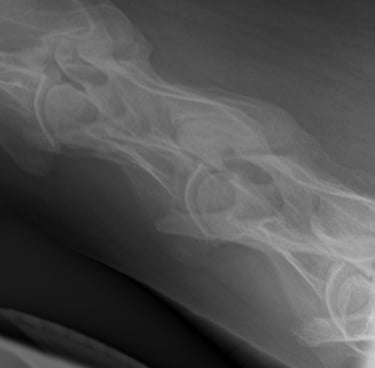

Is uw paard mank, hoefbevangen of is er een vermoeden van een halsprobleem? Dan kan het aangewezen zijn om een radiografisch onderzoek (RX) aan huis uit te voeren. Wij beschikken over een digitaal mobiel radiografietoestel, waardoor opnames eenvoudig bij u ter plaatse kunnen worden gemaakt.

Wij maken geen radiografische opnames in het kader van een radiografische keuring.

Dit onderzoek wordt uitgevoerd binnen een straal van 20 km rond de praktijk.

Radiografie (RX)

Consult op de praktijk of aan huis